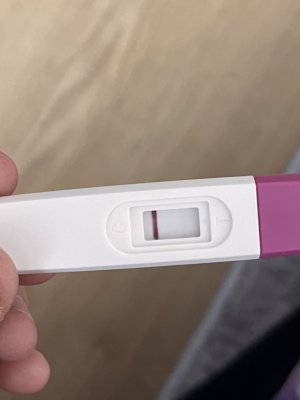

Kızlar merhaba bugün aşılamanın 11.günü yapıldığı günü saymazsam eğer , cuma günü kan vermiştim beta 0 çıkmıştı . Bugün bi test yapayım dedim testte böyle silik çizgi çıktı adetimi de tam kestiremiyorum pcos var bende 1-2 en fazla 3 gün kalmıştır. Testi ekliyorum böyle silik öğrenen varmı aranız da ?

Eklentiler

bence bebek var canım rabbim en hayırlısından nasip etsinKızlar merhaba bugün aşılamanın 11.günü yapıldığı günü saymazsam eğer , cuma günü kan vermiştim beta 0 çıkmıştı . Bugün bi test yapayım dedim testte böyle silik çizgi çıktı adetimi de tam kestiremiyorum pcos var bende 1-2 en fazla 3 gün kalmıştır. Testi ekliyorum böyle silik öğrenen varmı aranız da ?

Çok teşekkür ederim inşallahbence bebek var canım rabbim en hayırlısından nasip etsin